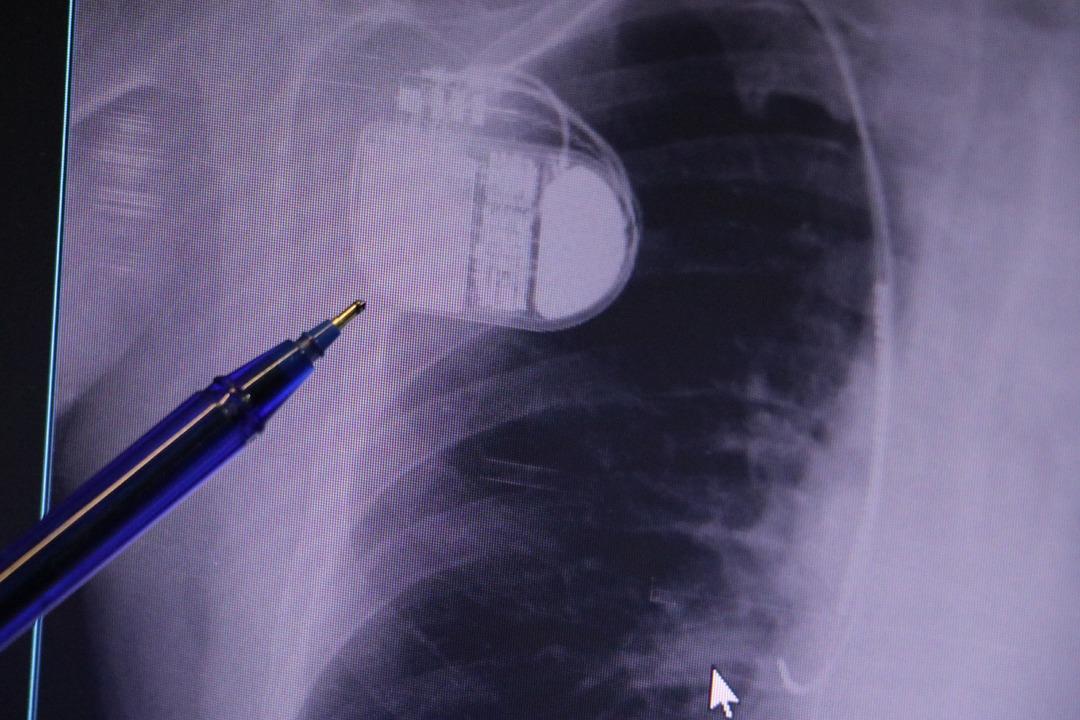

Konuyla ilgili açıklama yapan Kardiyoloji Anabilim Dalı Uzmanı Dr. İsmail Erdoğu, kalp pilinin önemine dikkat çekti. Yeni nesil kalp pillerinin MR cihazlarına erişim sağladığını ancak tarama cihazlarından geçmenin tavsiye edilmediğini söyleyen Erdoğu, şöyle konuştu: “Soğuktan kaynaklanan titreme, kalp pilinin kalbin durduğunu düşünmesine ve sahte şoka neden olabilir. Bu nedenle hastalarımıza bu dönemlerde daha dikkatli olmalarını öneriyoruz.”

MR makinesine kalp pili takılmasının mümkün olduğunu belirten Erdoğu, şöyle konuştu: “Çok büyük bir ameliyat değil ama yine de ciddi bir cerrahi işlem. Kalp pili tıpta son 30 yılın en büyük gelişmesi. Aslında bilgisayarın minyatürleştirilmiş hali olup insan vücuduna yerleştirilen bir tedavi. İnsan ömrünü önemli ölçüde uzatan bir tedavi. İnsanlar şokla hayata tutunurken, pil olmasaydı öleceğini düşündüğümüz çok sayıda hastamız var. Bu özelliğimiz Kalp pili uygun hastalarda ani ölümü önler, ritmi düzeltecek sağlık uzmanı ya da defibrilatör yoksa hastayı hayatta tutmak mümkün değildir. Hastalarımız “kalp pilim var” dediğinde hastalıktan kurtulurlar. Örneğin mikser kullanmak ya da kolu sallayacak herhangi bir hareket kalp pilini olumsuz etkileyebilir. Soğuk havalarda vücutta meydana gelen şiddetli titremeler kalp pilinin hafızasını karıştırıp gereksiz şoklara neden olabilir.